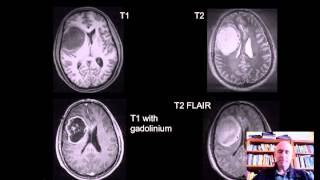

intraoperative neuropathology primer video

intraoperative neuropathology primer

intraoperative neuropathology primer Surgical neuropathology pearls: intraoperative consultations - Dr. Rodriguez (Hopkins) #NEUROPATH

intraoperative neuropathology primer

intraoperative neuropathology primer Surgical neuropathology pearls: intraoperative consultations - Dr. Rodriguez (Hopkins) #NEUROPATH